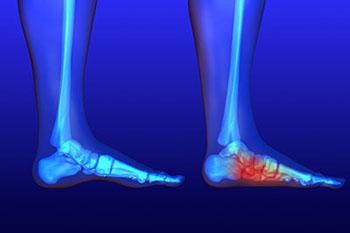

Flat Feet

Flat feet is a condition that affects those who have little to no arch in their feet. When you stand, a person who doesn’t have flat feet will have a gap from the inner part of their feet to the floor, due to the normal arch that slightly rises off the ground. Those...